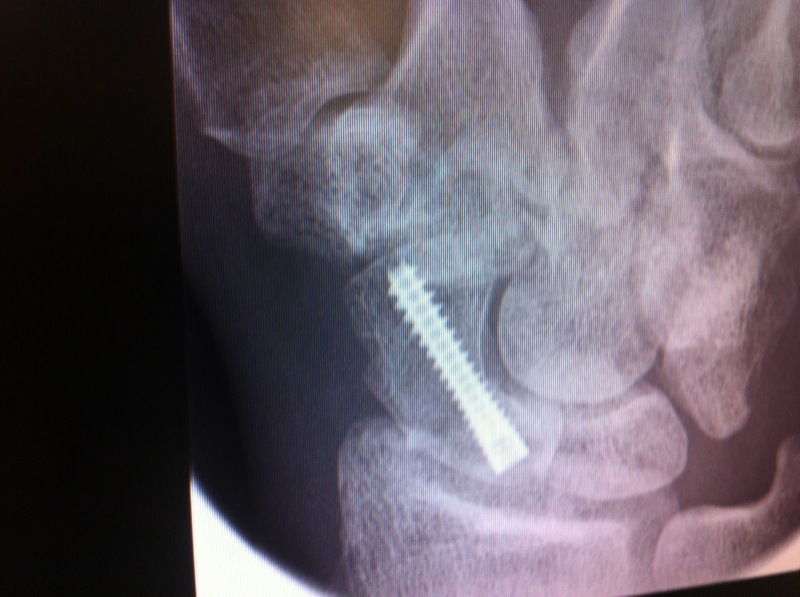

This news took me a while to come to terms with and at the time I felt devastated. I was able to look at my X-rays for the first time and I have to say I can’t see a crack in the bone anymore, just a ruddy great screw holding it all together. However, if I fall on my hand again, breaking my wrist, that means I would need another operation to remove the existing screw and I would also need a bone graft to be taken from my hip to aid the union. I have to wear this cast again over Christmas and my follow up appointment is on the 17th of January 2012. I hope that on this day I’ll lose the cast and be back on the bike.